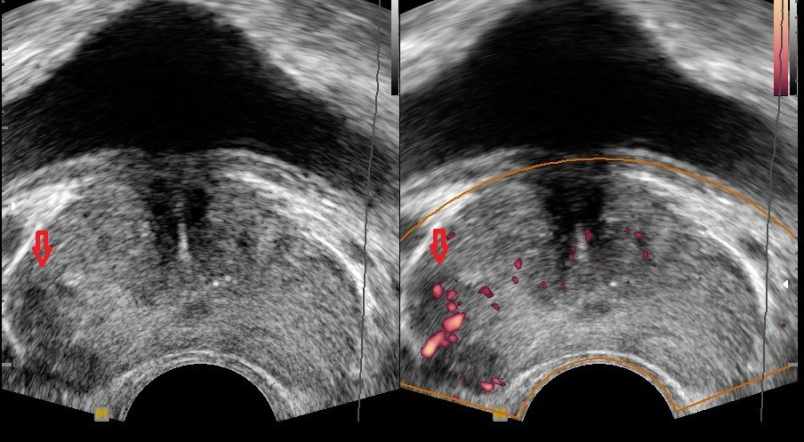

전립선암 초기증상 - 급성 요폐 (소변이 전혀 나오지 않음)

- 설명: 암 조직이 급격하게 커져 요도를 완전히 막아버릴 경우, 소변을 전혀 볼 수 없게 되는 급성 요폐가 발생할 수 있습니다. 이는 방광에 소변이 가득 차 극심한 통증을 유발하는 응급 상황으로, 즉시 병원을 방문하여 소변줄(카테터)을 삽입하여 소변을 빼줘야 합니다.